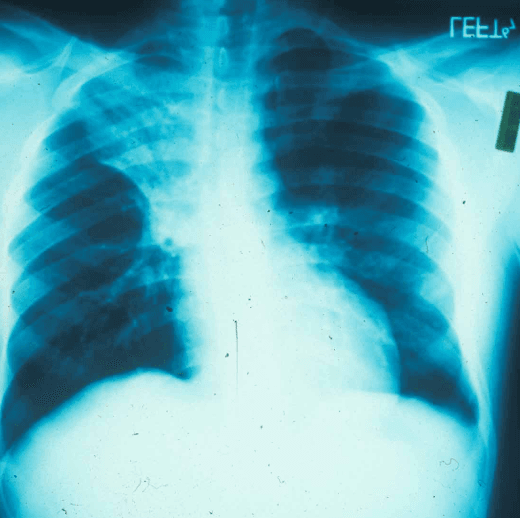

Chest radiography demonstrates a right upper lobe cavitary opacity with surrounding consolidation. Routine laboratory studies are largely unremarkable, and sputum cultures are unrevealing. Skin biopsy demonstrates broad-based budding yeast on Grocott methenamine silver staining, shown below. HIV fourth-generation testing is pending. Lumbar puncture is performed to assess for CNS involvement and is unremarkable.

Chest X-ray